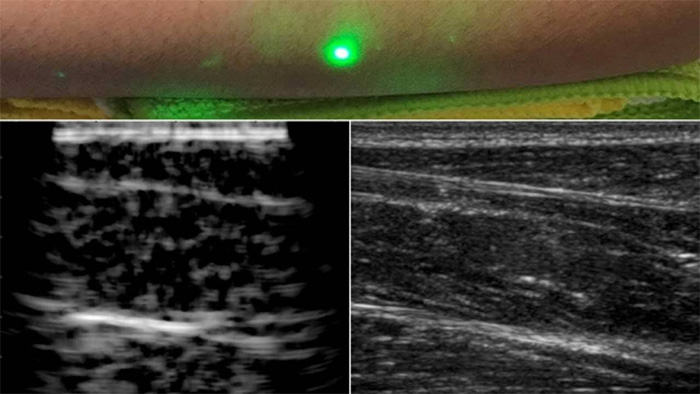

現(xiàn)在,麻省理工學(xué)院的科學(xué)家們找到了一個解決方案;他們已經(jīng)開發(fā)了一種新的激光超聲波技術(shù),一種不需要與身體接觸就能看到病人內(nèi)部的超聲波技術(shù)。該方法利用對眼睛和皮膚均安全的激光系統(tǒng)遠(yuǎn)程成像人體內(nèi)部。

為了進(jìn)行測試,科學(xué)家們對幾名志愿者的前臂進(jìn)行了成像,并觀察了皮膚以下約6厘米處的肌肉、脂肪和骨骼等常見組織特征。這些圖像與傳統(tǒng)的超聲波類似,是用遠(yuǎn)程激光聚焦在半米外的志愿者身上產(chǎn)生的。

科學(xué)家們用一臺1550納米的脈沖激光來產(chǎn)生聲波,另一臺調(diào)到相同波長的連續(xù)激光來遠(yuǎn)程探測反射聲波。這第二層是一個靈敏的運(yùn)動探測器,它測量由聲波反射到肌肉、脂肪和其他組織引起的皮膚表面振動。反射聲波產(chǎn)生的皮膚表面運(yùn)動引起激光頻率的變化,可以測量。通過機(jī)械地掃描全身的激光,科學(xué)家可以在不同的位置獲取數(shù)據(jù),并生成該區(qū)域的圖像。